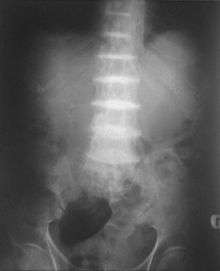

After the age of thirty people begin to develop pain in the weight-bearing joints of the spine, hips and knees. The pain can be severe to the point that interferes with activities of daily living and may affect ability to work. Joint replacement surgery (hip and shoulder) is often necessary at a relatively young age.[1] In the longer term, the involvement of the spinal joints leads to reduced movement of the rib cage and can affect breathing.[1] Bone mineral density may be affected, increasing the risk of bone fractures, and rupture of tendons and muscles may occur.[1]

The homogentisic acid is converted to the related substance benzoquinone acetic acid (BQA) which forms polymers that resemble the skin pigment melanin. These are deposited in the collagen, a connective tissue protein, of particular tissues such as cartilage. This process is called ochronosis (as the tissue looks ochre); ochronotic tissue is stiffened and unusually brittle, impairing its normal function and causing damage.[1]